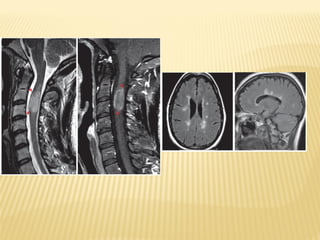

Trata-se de uma doença inflamatória crónica desmielinizante e

degenerativa do sistema nervoso central que interfere com a

Denomina-se Esclerose pelo facto de, em resultado da

doença, se formar um tecido parecido com uma cicatriz, que

endurece, formando uma placa em algumas áreas do

cérebro e medula espinal.

Denomina-se Múltipla, porque várias áreas dispersas do

cérebro e medula espinal são afectadas.